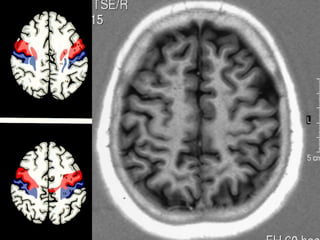

Lobo frontal

• 3 sulcos / 4 giros .

• Sulcos pré central , frontal superior e inferior .

• Giros frontal superior , médio e inferior e

giro frontal ascendente ( pré central )       principal

área somato motora cortical

Giro

Reto

Orbitário

Frontal

Superior

Médio

Inferior